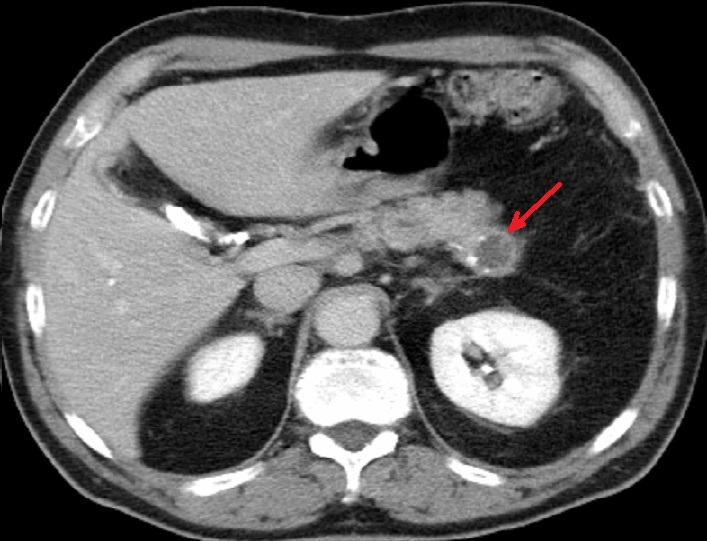

Image radiologique IRM d'une

cystarenome mucineux du pancreas avec aspect

lesionaire de kyste ovalaire uniloculaire a

hyposignal ( fleche rouge ) . Coupe axiale IRM

ponderee T1 |

Meme cas en coupe IRM axiale

ponderation T2 . La tumeur kydtique devient tres

hyperintense ( fleche rouge ) |

|